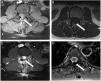

ResultsThe mean follow-up period was 27 months. No patient developed a post-operative cerebrospinal fluid (CSF) dural-cutaneous fistula. CSF leakage was not observed in the control MRIs at 6 weeks.

ConclusionsWe describe, for the first time, the use of this type of U-clip with a flat inner side. The non-penetrating titanium U-clip facilitates effective and rapid dural closure at all spinal levels due to its flat internal face when closed. The U-clips did not cause significant artefacts or distortions on the magnetic resonance imaging.